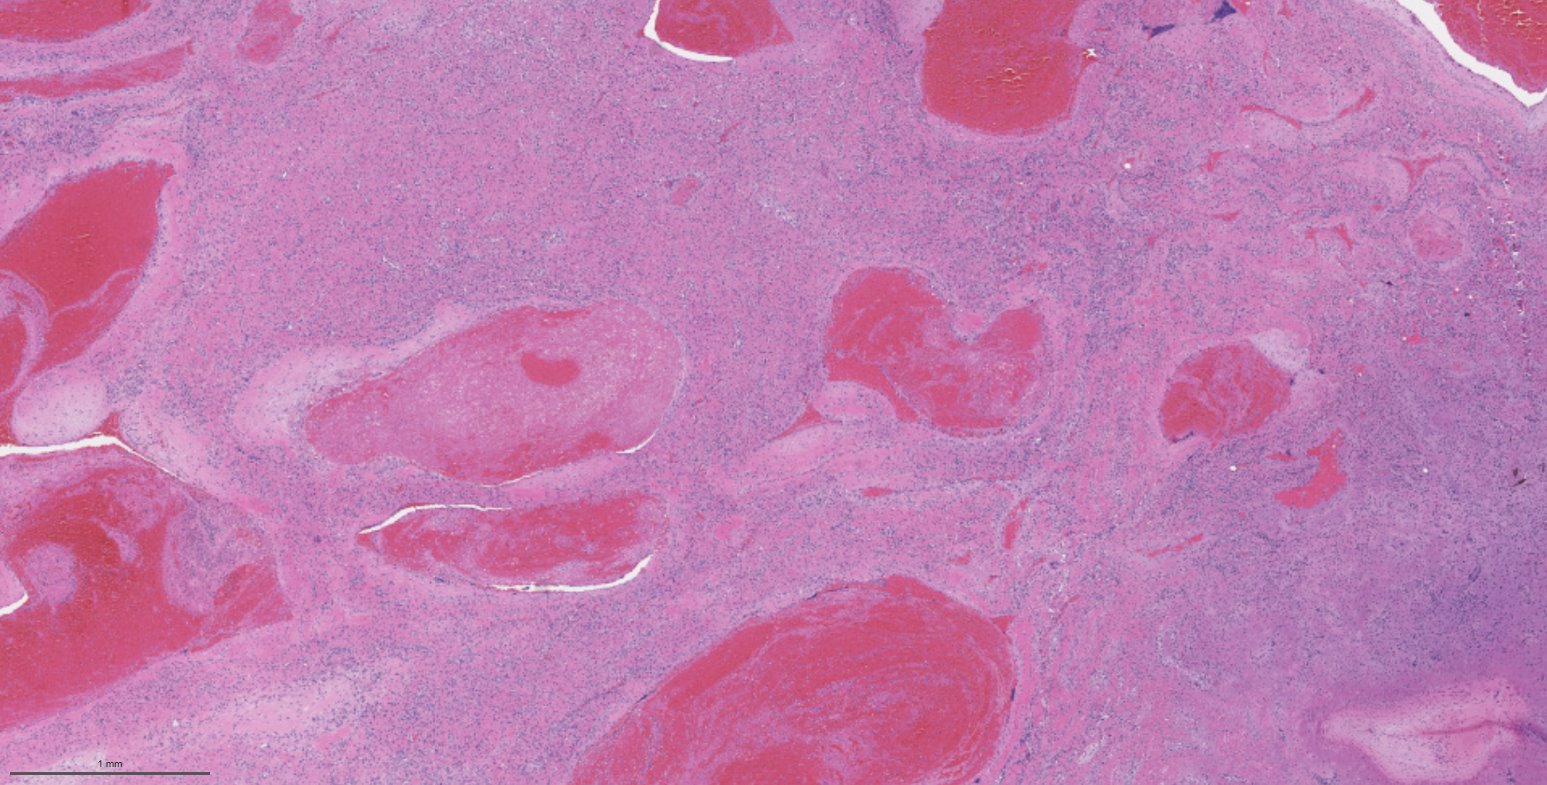

Microscopic (histologic) description

- Benign fibrovascular lesion composed of 2 components

- Vascular space of various sizes, ranging from dilated branching vessel of various thickness to slit-like capillaries

- Fibrous or collagenous stroma with fibroblasts

- Central area of the tumor is typically cellular, composed of fibroblasts or myofibroblasts with spindle, round or stellate morphology

- Stroma can be fibrous, edematous or collagenized

- Fibrinous thrombi may be seen in dilated vessels

- Frequently contain (abundant) mast cells

Microscopic (histologic) images

Contributed by Bin Xu, M.D., Ph.D.

Contributed by Kelly Magliocca, D.D.S., M.P.H.